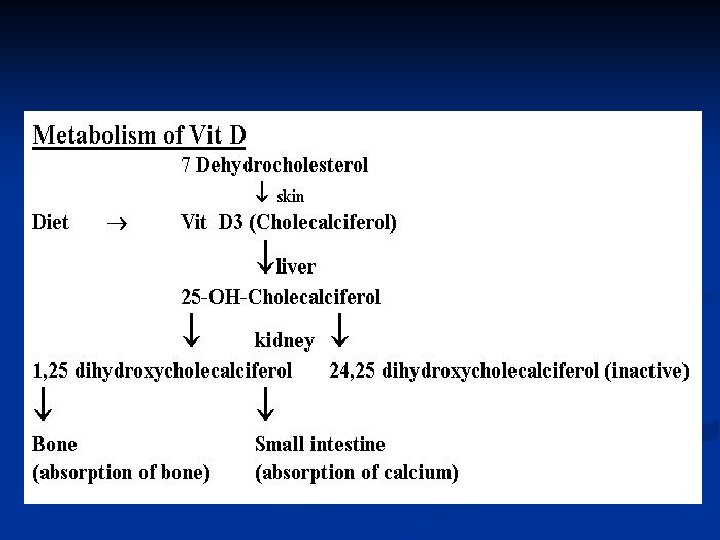

Biochemistry of Vitamin D 3 – Brief Review Vitamin D 3 (cholecalciferol) is synthesized in the skin, with UV light, from 7 -dehydrocholesterol n Vitamin D 3 is hydroxylated twice – first in the liver, to 25 hydroxycholecalciferol, then in the kidney, to 1, 25 dihydroxycholecalciferol, the most potent form of Vitamin D n

Vitamin D metabolism

Vitamin D Metabolism